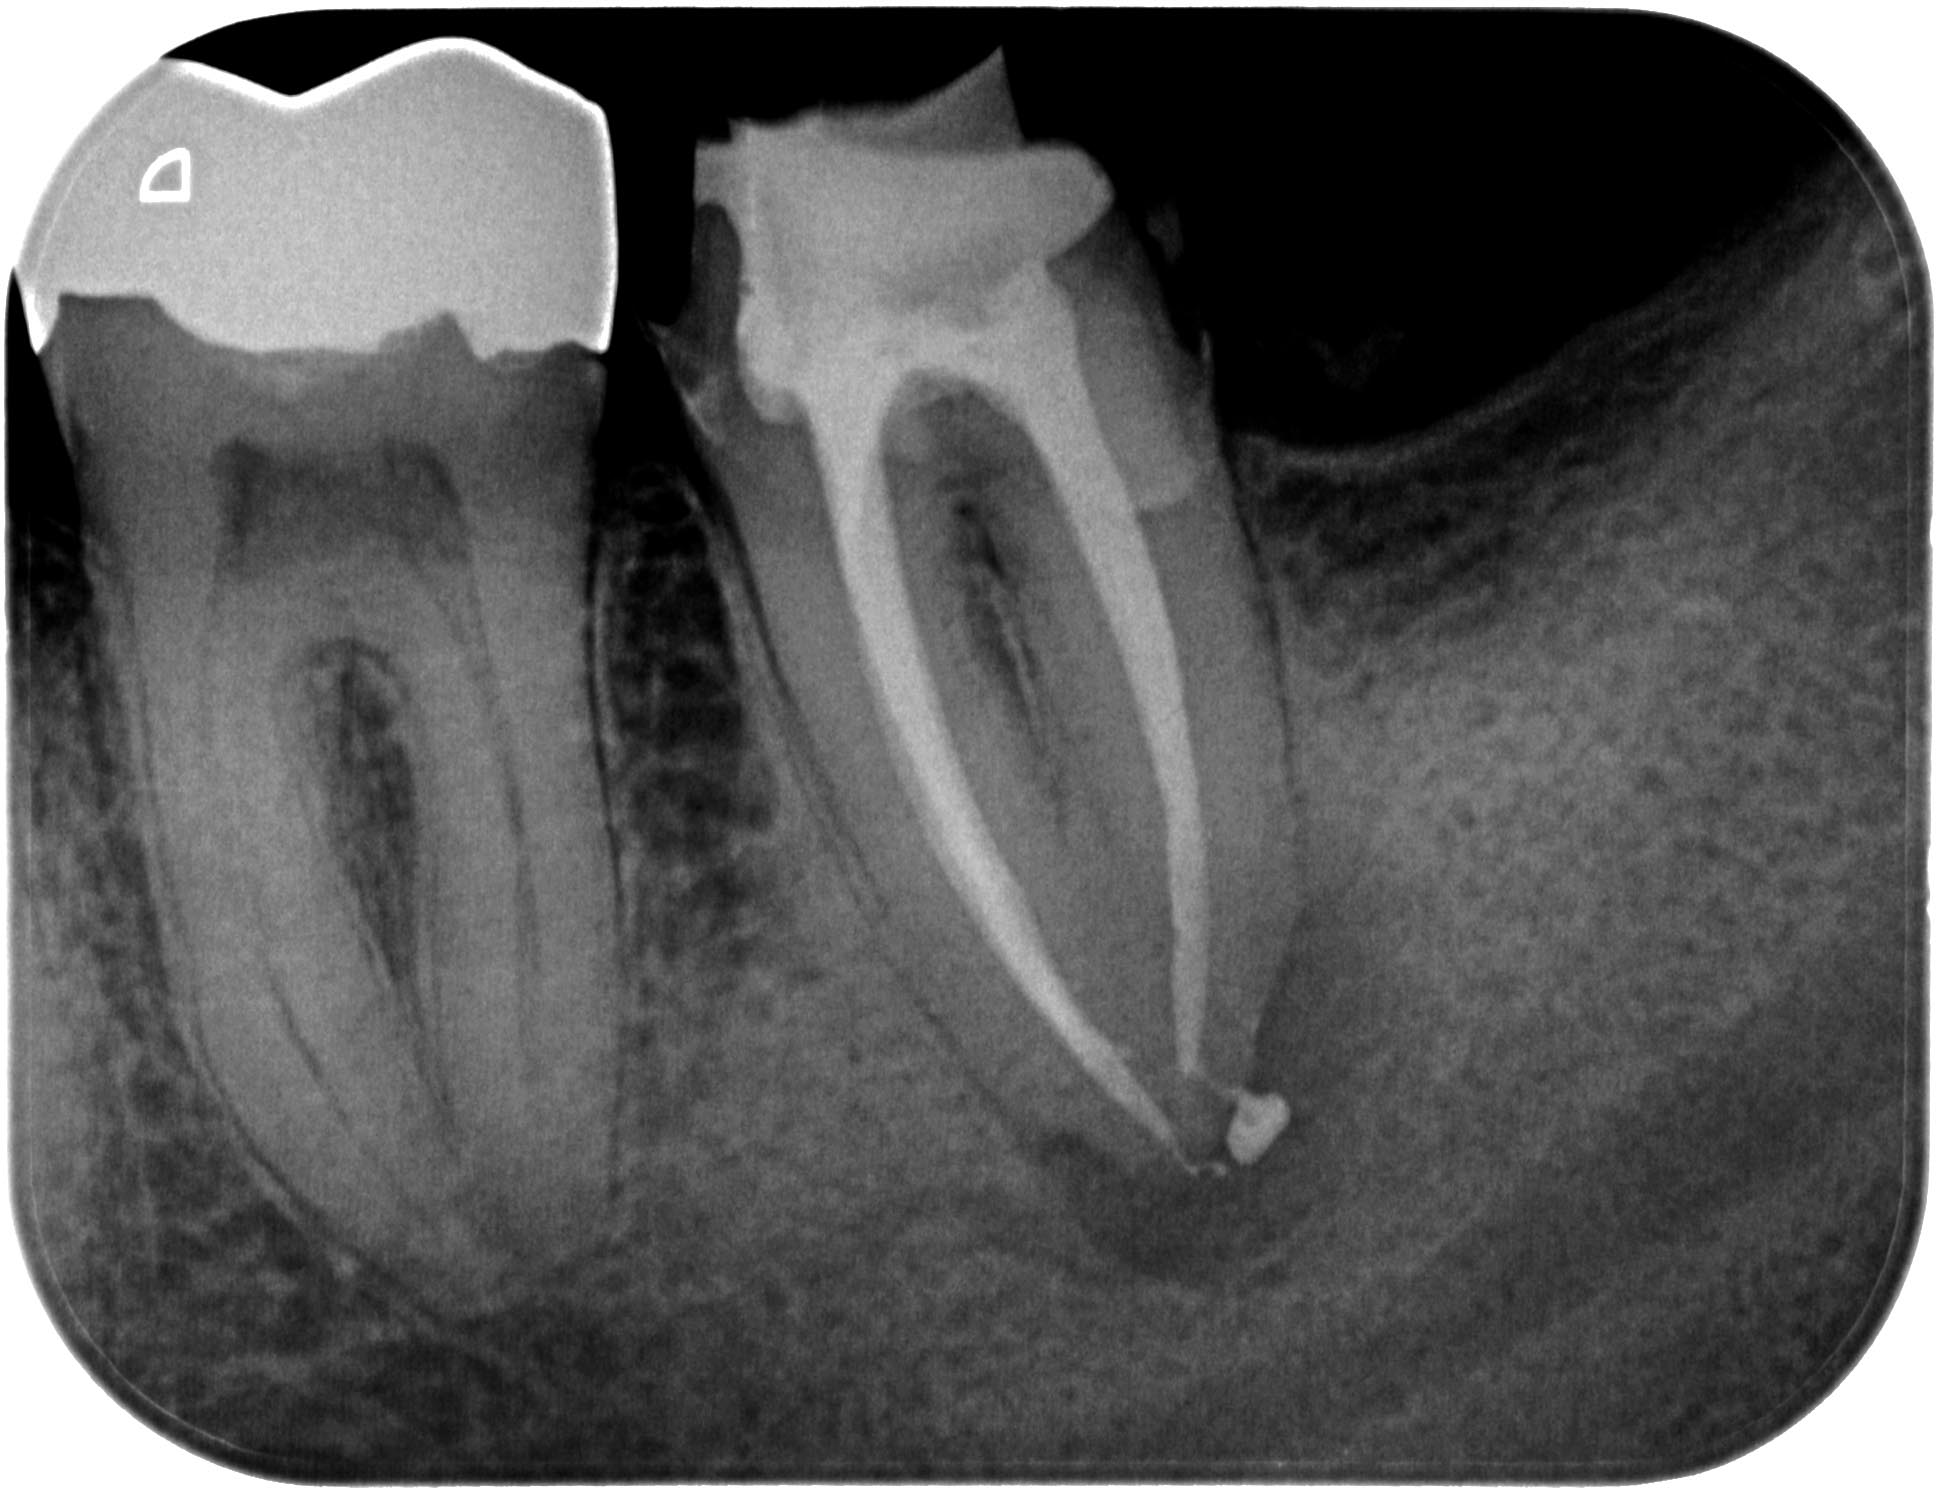

KSKrone6MonatepostWF-1-3 Veröffentlicht 24. September 2015 am 1938 × 1488 in Zuverlässige Endometrie bei Metallkronen – aber auch – Wäre das nicht eine sinnvolle neue Rubrik für WURZELSPITZE ? Zahn 37 WF